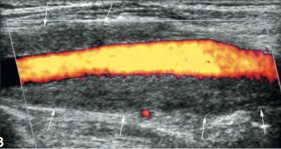

Normal thyroid US appearance

• Homogeneous parenchyma

• Medium-high level echoes (hyperechoic to straps muscles)

• Thin hyperechoic capsule

• Vascular (uniformly distributed)